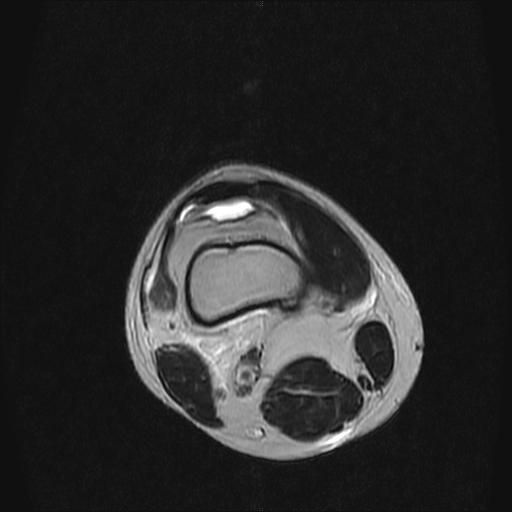

标题: MRI1265:男性40岁,右膝关节 [打印本页]

标题: MRI1265:男性40岁,右膝关节

40岁男性,右膝关节外伤,x光平片示,髁间隆突撕脱骨折。

1、前交叉韧带撕裂;

2、外侧半月板后角撕裂;

3、关节腔积液。

前交叉韧带撕裂,关节腔积液.

半月板1-2级损伤   前交叉韧带撕裂伤   关节腔少量积液  诸骨未见新鲜外伤性改变

髁间隆突撕脱骨折;内侧副韧带损伤。

1、内侧副韧带撕裂;

2、前交叉韧带撕裂;

3、滑膜炎伴关节腔积液。

内侧副韧带撕裂及关节腔积液是肯定的,但是前交叉撕裂确定吗?会不会有容积效应的因素,因为前一张前交叉显示清楚,连续性良好,且较光滑。请问楼主有关节镜支持吗?我们医院也经常有这样的患者,但苦于没有关节镜,而无法对照、证实(除非完全断裂),出现了不同的诊断结果只能毫无意义的争论。

除了关节积液外并无韧带撕裂,acl胫侧附着点有2束,正常情况下脂肪信号。此病例应加做压脂像以便观察是否有骨损伤。